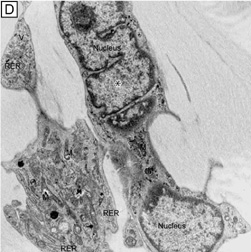

The endothelium of the infant cornea is composed of a single layer of approximately 500,000 neural crest-derived cells, each measuring around 5 μm in thickness by 20 μm in diameter and cover a surface area of 250 μm2.58,85 The cells lie on the posterior surface of the cornea and form an irregular polygonal mosaic. The tangential appearance of each corneal endothelial cell is uniquely irregular, usually uniform in size to one another, and typically six-sided (i.e., hexagons). They abut one another in an interdigitating fashion with 20 nm wide intercellular space between each other. The intercellular space is known to contain discontinuous apical tight junctions (macula occludens) and lateral gap junctions, thereby forming an incomplete barrier to diffusion of small molecules. As corneal endothelial cells have numerous cytoplasmic organelles, particularly mitochondrial organelles, they have been inferred to have the second highest aerobic metabolic rate of cells in the eye next to retinal photoreceptors.58

Having a sufficient number of endothelial cells to cover the posterior surface of the cornea along with having integrity of their cell junctions (tight and gap junctions), which are present in the intercellular spaces between endothelial cells, establishes the barrier function of endothelium (Figs. 12 and 22, 23, and 24). Clinically, the barrier function of the cornea can be assessed in vivo by the use of specular microscopy or confocal microscopy (endothelial cell density) or fluorophotometry (permability). In healthy human eyes, this barrier prevents the bulk flow of fluid from the aqueous humor to the corneal stroma, but does allow moderate diffusion of nutrients, water, and other metabolites to cross into the stroma through the 20 nm wide intercellular space. This leaky endothelial barrier may initially seem inefficient, but when one considers that most nutrients for all layers of the cornea come from the aqueous humor, the situation is reasonable.

Fig. 23. Scanning electron micrograph (1,000×) on the posterior surface of the corneal endothelium from a 65-year-old patient with healthy eyes. Note how the hexagonal endothelial cells form a uniform monolayer. Bar = 10 μm.

Fig. 24. Transmission electron micrograph (15,000×) of corneal endothelium from a specimen specially-preserved (glutaraldehyde + cetylpyridium chloride) and stained (tannic acid) to show the glycocalyx of the endothelium. NBDM, nonbanded Descemet's membrane; E, endothelial cells. Bar = 1 μm.